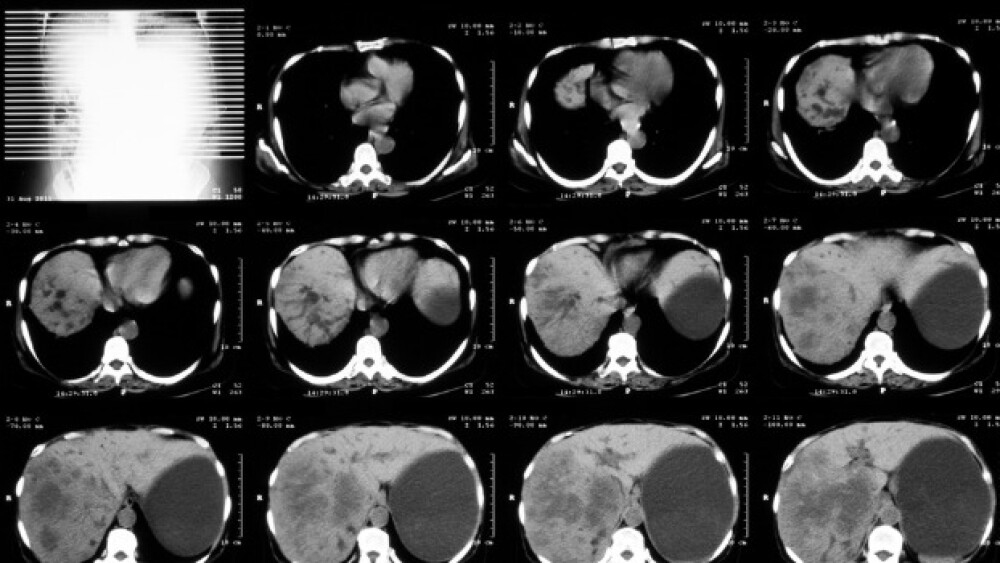

Results of a Phase IIb trial of the company’s anti-TL1A antibody showed more than a third of ulcerative colitis patients entered remission while receiving the experimental treatment.